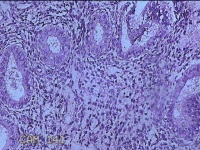

子宫腔内容物

性别

女

年龄

33岁

临床诊断

子宫内膜息肉?子宫异常出血

一般病史

阴道流血12天。

标本名称

大体所见

;纱布一块,内有灰白暗红色不规则碎组织3.5x2.8x1.3cm一堆。

图2